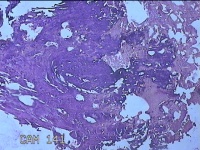

肛门肿物

性别

女

年龄

41岁

临床诊断

混合痔

一般病史

发现肛门肿物突出伴大便带血2年。

标本名称

大体所见

灰白暗红色皮肤肿物1.5x1.3x0.3cm一个,表面糜烂,切面灰白粉红色,质软。

建议:技术组派出去进修三个月。